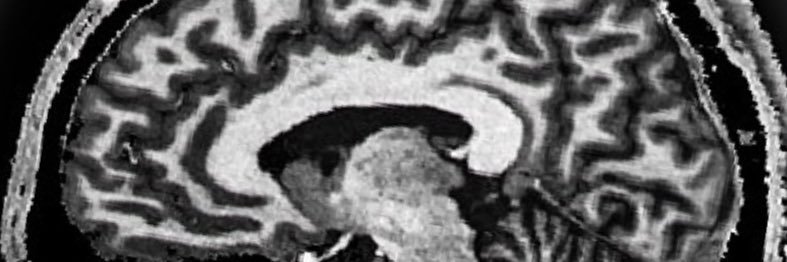

Cognitive neuroscience of visual mental imagery, aphantasia and consciousness.